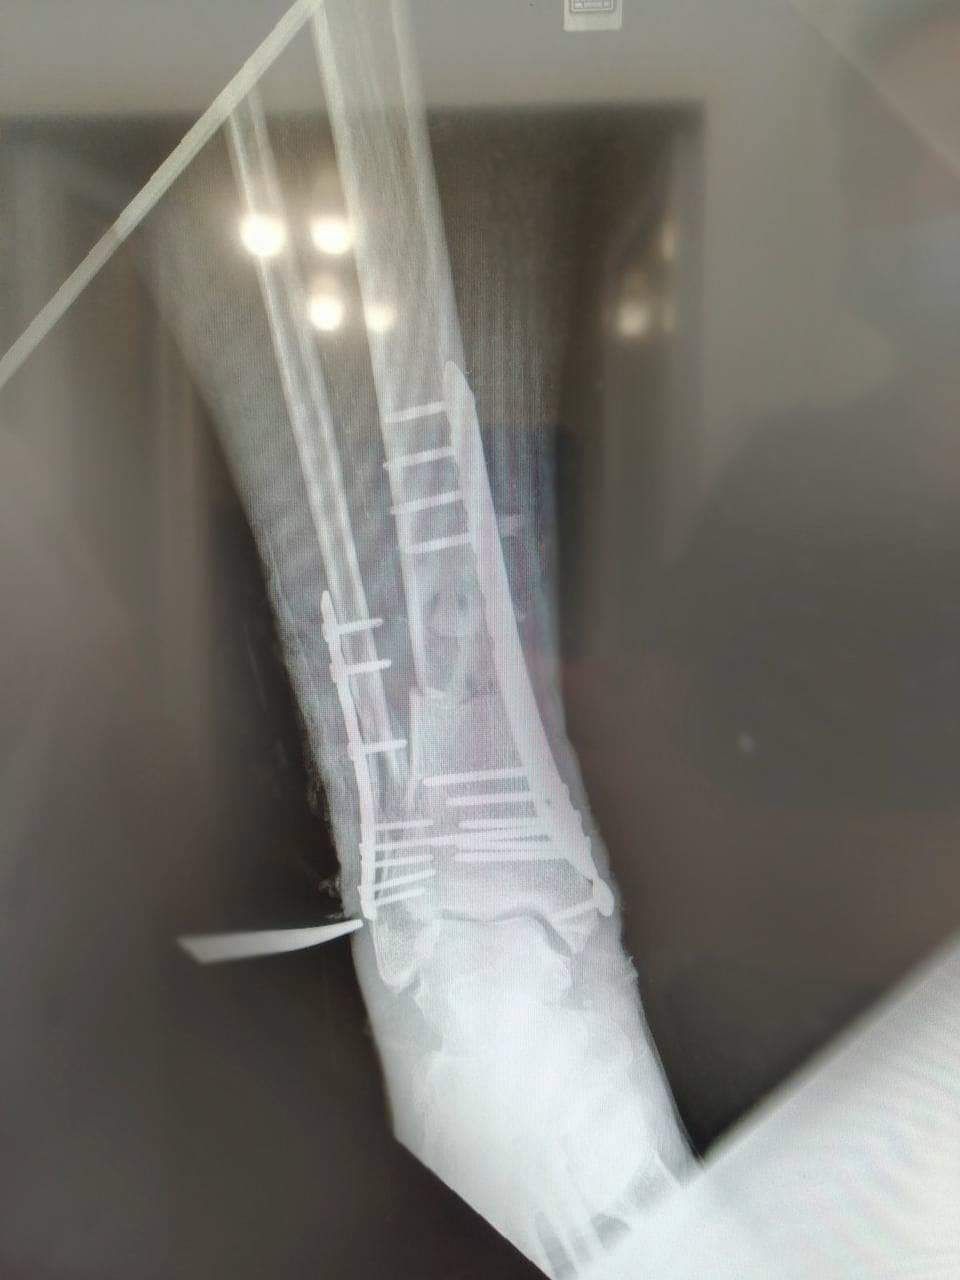

У травматологічне відділення він потрапив у важкому стані. Права нога зламана, ушкоджені обидві кістки. На лівій – рана, серйозний дефект тканин. За довгий час поневірянь та пошуків допомоги шкіра почала відмирати. У ранах залишилися шматки деревини та одягу ще після вибуху. Лікарям здавалося, що врятувати його просто неможливо.

За рахунок благодійного фонду придбали металоконструкції та встановили на кістки. Дідусь переніс 2 важкі операції. Близько місяця провів у лікарні, поки не загоїлись всі рани. Почав ходити.